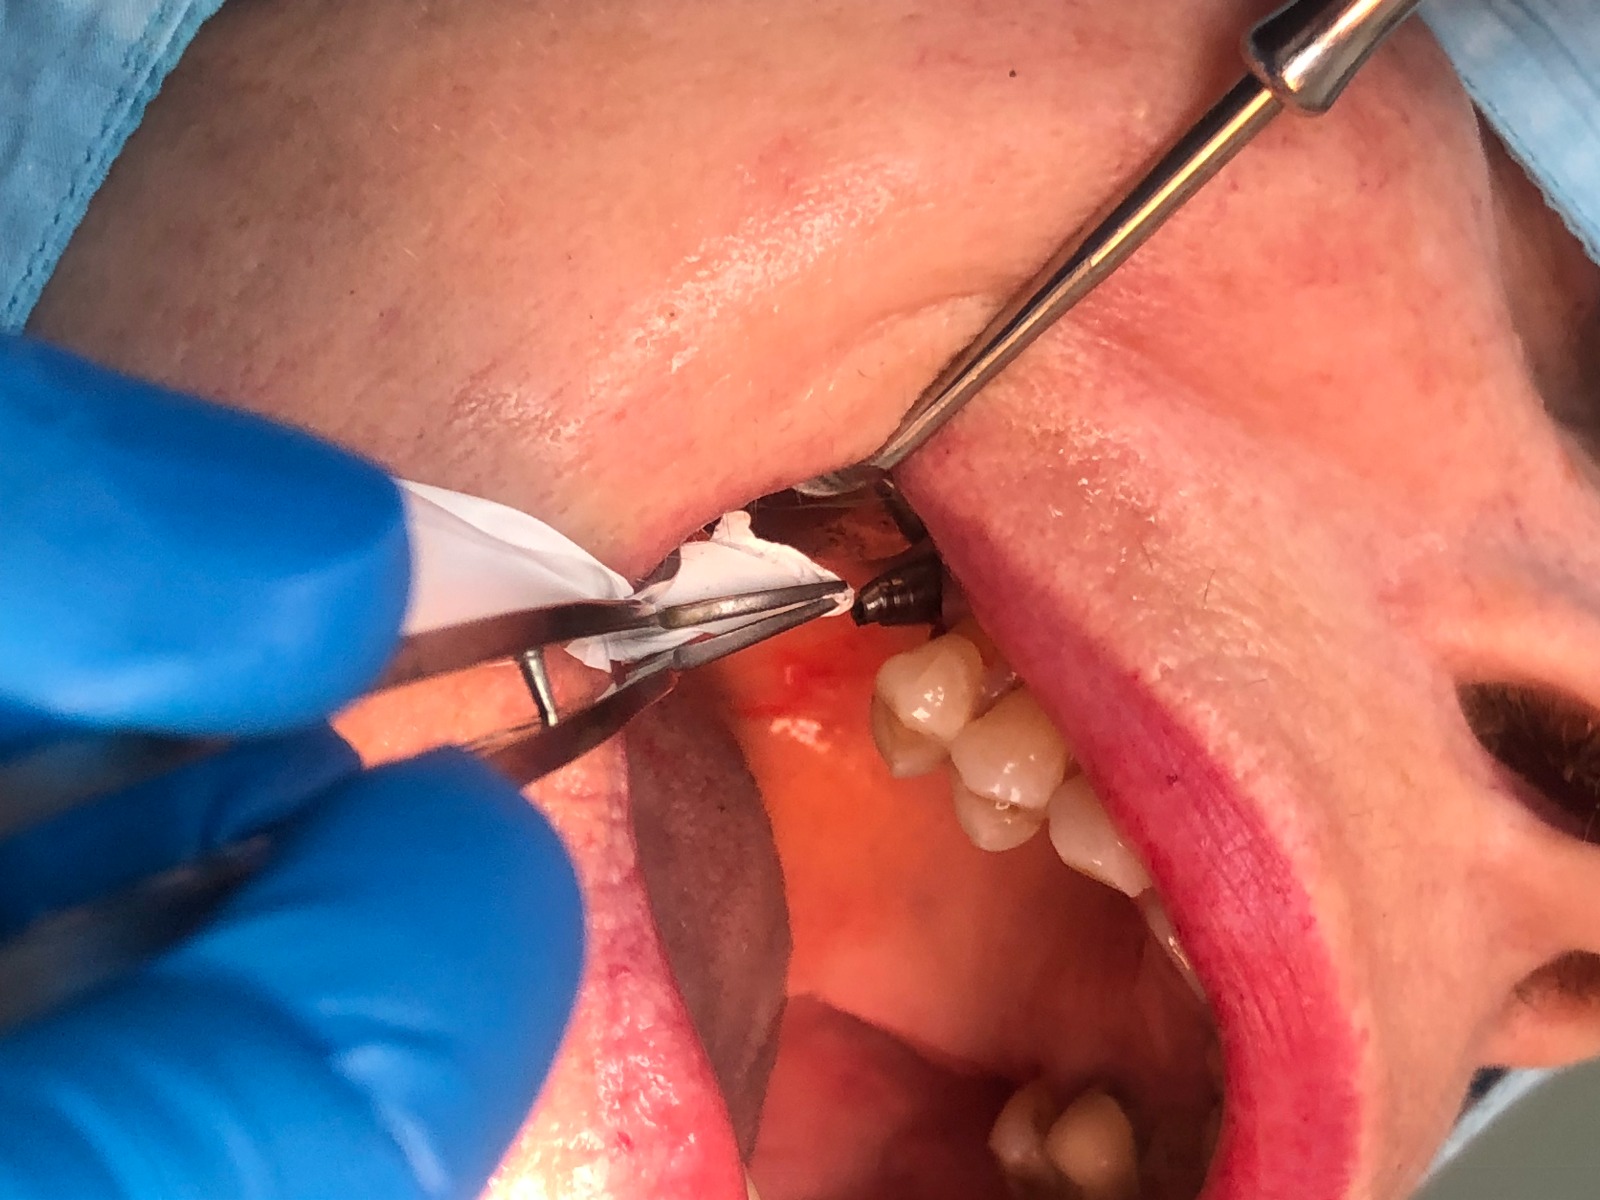

Debido a que la rosca no salió con la vibración optamos por rehacerla. Primero, procedemos al vaciado del implante con las fresas cañón estándar. Y continuación, realizamos el paso sucesivo de los machos de roscar por dentro del vaciado conseguido. Finalmente hemos rehecho la rosca.

Exponemos nuevo caso de paciente con una fractura del tornillo pasante sobre un implante unitario molar. El tornillo pasante es la parte fundamental de la conexión y es el que está roto dentro y gripado, de tal forma que no pudimos extraer con el aparato de ultrasonido.